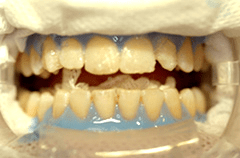

Abb. links Aufgetragenes Gingivaschutzgel (blau) und Bleichgel (auf dem Zahn).

Die Gingiva wird nach Isolierung des Arbeitsfeldes mit einem speziellen Schutzgel abgedeckt, um die Schleimhaut zu schonen. Um das optimale Ergebnis nach Auftragen des Bleichgels zu erhalten, empfiehlt sich die Verwendung einer speziellen Bleichlampe. Sie sollte ein exakt justierbares und genügend großes Belichtungsfenster besitzen, um ein gleichmäßig intensives Aufhellen der oberen und unteren Zahnreihe zu ermöglichen (wie z.B. die Metall-Halogenidlampe der Firma Discus Dental). Sollte während des Bleichvorganges trotz Schutz des Zahnfleisches und freiliegender Zahnhälse ein blitzartiges Ziehen an einem Zahn mit Füllung auftreten, ist das ein sicherer Hinweis dafür, dass die Füllung einen eventuell röntgenologischen nicht sichtbaren Randspalt aufweist. Füllungen sollten daher generell vor einem Bleaching abgedichtet werden. Die definitive Versorgung durch Schmelz-/Dentinadhäsion sollte etwa zehn Tage nach dem Bleichen durchgeführt werden, da dann der Zahn wieder komplett remineralisiert ist und daher wieder eine optimale adhäsive Verankerung und auch passende Farbauswahl möglich ist. Die bei uns im Hause zahlreich durchgeführten In-Office-Bleaching Sitzungen mit dem ZOOM® Zahnnaufhellungssystem führten in keinem Fall zu deutlicher Postsensibilität der Zähne, und kann daher aus meiner Sicht uneingeschränkt für das schnelle, wirkungsvolle und dennoch schonende In-Office-Bleaching  empfohlen werden.